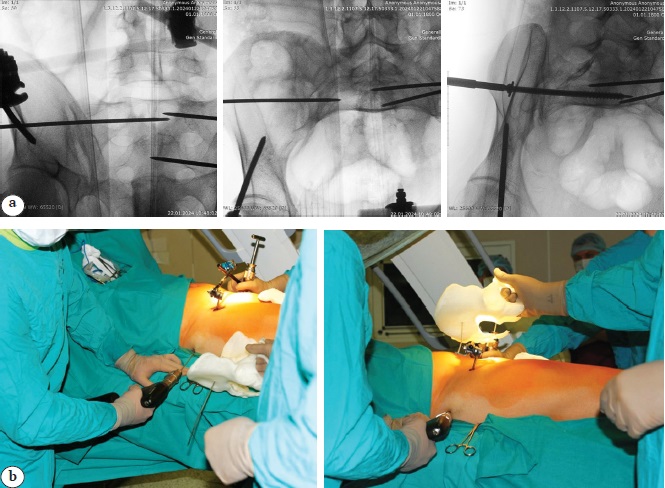

The patient was positioned supine on a radiolucent operating table. A urinary catheter was inserted prior to the procedure to prevent iatrogenic injury. A pre-sterilized 3D-printed pelvic model with marked trajectories and implant entry points was prepared, along with printed fluoroscopic images showing the placement of previously inserted fixators or guiding wires in various projections.

Fluoroscopic control of the guiding wires and implants, and their comparison with the 3D model was performed throughout the procedure in standard views: inlet, outlet, anteroposterior, lateral, obturator, and iliac (according to Judet).

Through small skin incisions of 1.0-1.5 cm, guiding wires were introduced into various pelvic bone structures. Navigation was performed by comparing the wire positions and angles with the 3D model and by assessing the spatial orientation of the surgeon’s hands (Figure 5).

Figure 5. Intraoperative navigation: a — X-ray control; b — using a 3D model during surgery

Adjustments to wire placement were made as necessary, followed by repeated comparison with the 3D model. Then, in accordance with the preoperative plan, definitive hardware fixation was carried out: cannulated screws (6.5 or 7.3 mm, fully or partially threaded, with/without washers), a locking nail in the pubic bones, and 3.5 mm stainless steel cortical screws. Implant orientation in the patient’s pelvic bones was compared with the pre-set implants in the plastic model. Final fluoroscopic control was performed, followed by suturing and application of aseptic dressings. If previously used, the external fixator was removed at this stage.